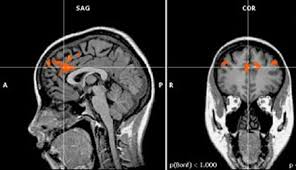

Anterior Cingulate Cortex Fmri, Fmri Test Result Depicting Brain Activities Mapping 3 Anterior Download Scientific Diagram, Numerous studies have identified the medial frontal cortex (mfc), and especially its anterior cingulate part (acc), as one of the most reliable neural correlates of cognitive control in the human brain (carter et al.. The anterior cingulate cortex (acc) plays an important role in attentional control, but the spatiotemporal dynamics underlying this process is poorly understood. It consists of brodmann areas 24, 32, and 33. The anterior cingulate cortex (acc), a central hub for cognitive processing, is one of the brain regions known to be dysfunctional in schizophrenia. In addition, altered serotonergic neurotransmission has been repeatedly implicated in the pathophysiology of migraine, although the exact mechanism is not known. Previous research has found that these adjustments are most robust in the simon task.

The current functional magnetic resonance imaging (fmri) study of word generation was designed to determine which of these three functional domains was substantially involved by mapping individual subjects' functional activity onto structural images of their left medial frontal cortex. A growing body of literature has implicated the medial frontal cortex (mfc), and specifically the anterior cingulate cortex (acc), in processing social value. Studies have shown heightened activity in the anterior cingulate cortex, frontal cortex, and prefrontal cortex, specifically in the dorsal medial prefrontal area during vipassana meditation. Several structural and functional alterations of this brain area have been found in migraine. Pregenual anterior cingulate cortex (pacc) is an important midline structure involved in emotional processing and affect regulation and plays an essential role in depression neurocircuitry.

Previous research has found that these adjustments are most robust in the simon task. The current functional magnetic resonance imaging (fmri) study of word generation was designed to determine which of these three functional domains was substantially involved by mapping individual subjects' functional activity onto structural images of their left medial frontal cortex. The accd (cytoarchitectural areas 24b′/24c′/32′) is a functional subdivision of the anterior cingulate cortex that plays a critical role in complex cognitive/attentional processing badgaiyan and posner 1998, bush et al 1998, casey et al 1997b, devinsky et al 1995, mayberg 1997, mega et al 1997, paus et al 1998, posner and petersen 1990, vogt et al 1992, vogt et al 1995. Numerous studies have identified the medial frontal cortex (mfc), and especially its anterior cingulate part (acc), as one of the most reliable neural correlates of cognitive control in the human brain (carter et al. Milham mp (1), banich mt. The anterior cingulate cortex (acc) is a key structure of the pain processing network. Theories of anterior cingulate cortex (acc) emphasize a role for this brain area in performance monitoring 1 and action selection 2.one recent theory proposes that an area in caudal and dorsal acc. Anterior cingulate cortex from wikipedia, the free encyclopedia in the human brain, the anterior cingulate cortex (acc) is the frontal part of the cingulate cortex that resembles a collar surrounding the frontal part of the corpus callosum.

As a relatively new technology, fmri has only recently been used to assess brain state changes during meditation. Anterior cingulate cortex from wikipedia, the free encyclopedia in the human brain, the anterior cingulate cortex (acc) is the frontal part of the cingulate cortex that resembles a collar surrounding the frontal part of the corpus callosum. Ridderinkhof, van den wildenberg, et al. A growing body of literature has implicated the medial frontal cortex (mfc), and specifically the anterior cingulate cortex (acc), in processing social value. The anterior cingulate cortex (acc) plays an important role in attentional control, but the spatiotemporal dynamics underlying this process is poorly understood. In addition, altered serotonergic neurotransmission has been repeatedly implicated in the pathophysiology of migraine, although the exact mechanism is not known. In this event‐related functional magnetic resonance imaging (fmri) study, we provide evidence that the role of the anterior cingulate cortex (acc) in cognitive control may not be unitary, as the responses of different acc subregions vary depending upon the nature of task‐irrelevant information. Several theories have proposed that the acc acts as a bridge between attentional and emotional processing (bush et al., 2000, devinsky et al., 1995). It consists of brodmann areas 24, 32, and 33. The current functional magnetic resonance imaging (fmri) study of word generation was designed to determine which of these three functional domains was substantially involved by mapping individual subjects' functional activity onto structural images of their left medial frontal cortex. The anterior cingulate cortex (acc) plays an important role in attentional control, but the spatiotemporal dynamics underlying this process is poorly understood. Previous research has found that these adjustments are most robust in the simon task. The anterior cingulate cortex (acc) lies in a unique position in the brain, with connections to both the emotional limbic system and the cognitive prefrontal cortex.

Control subjects, cingulate cortex was one of only four (out of a total of sixty) regions interrogated that still showed regional hypoactivity after global normalization. It consists of brodmann areas 24, 32, and 33. The anterior cingulate cortex (acc) plays an important role in attentional control, but the spatiotemporal dynamics underlying this process is poorly understood. Abstract in this event‐related functional magnetic resonance imaging (fmri) study, we provide evidence that the role of the anterior cingulate cortex (acc) in cognitive control may not be unitary, as the responses of different acc subregions vary depending upon the nature of task‐irrelevant information. Numerous studies have identified the medial frontal cortex (mfc), and especially its anterior cingulate part (acc), as one of the most reliable neural correlates of cognitive control in the human brain (carter et al. An fmri analysis of conflict specificity and functional differentiation. As a relatively new technology, fmri has only recently been used to assess brain state changes during meditation. Theories of anterior cingulate cortex (acc) emphasize a role for this brain area in performance monitoring 1 and action selection 2.one recent theory proposes that an area in caudal and dorsal acc. Ridderinkhof, van den wildenberg, et al. The anterior cingulate cortex (acc), a central hub for cognitive processing, is one of the brain regions known to be dysfunctional in schizophrenia. In this event‐related functional magnetic resonance imaging (fmri) study, we provide evidence that the role of the anterior cingulate cortex (acc) in cognitive control may not be unitary, as the responses of different acc subregions vary depending upon the nature of task‐irrelevant information. Milham mp (1), banich mt. The current functional magnetic resonance imaging (fmri) study of word generation was designed to determine which of these three functional domains was substantially involved by mapping individual subjects' functional activity onto structural images of their left medial frontal cortex.